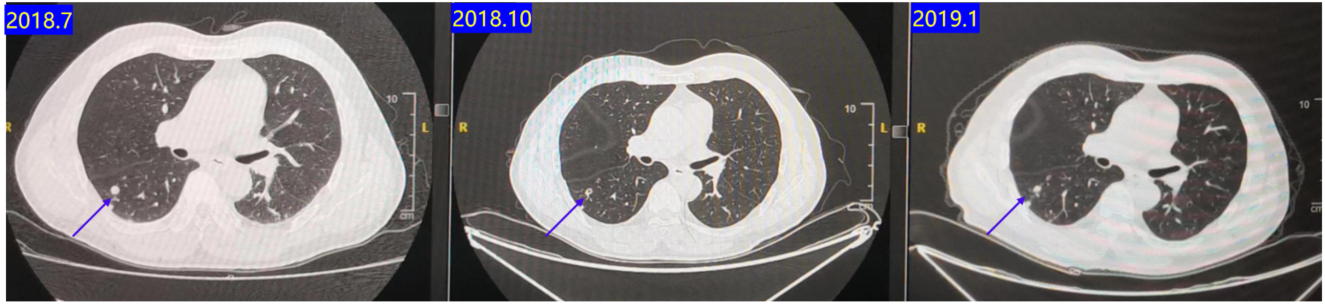

2018.08-2018.12:行FOLFOX + 贝伐珠单抗治疗8周期。

2019.01:行贝伐珠单抗 + 卡培他滨维持治疗2周期。疗效评估:治疗期间最佳疗效为疾病稳定(SD)(图2)

2019.08:复查CT提示肺部转移灶进展(图3),疗效评价为疾病进展(PD),PFS 12个月。